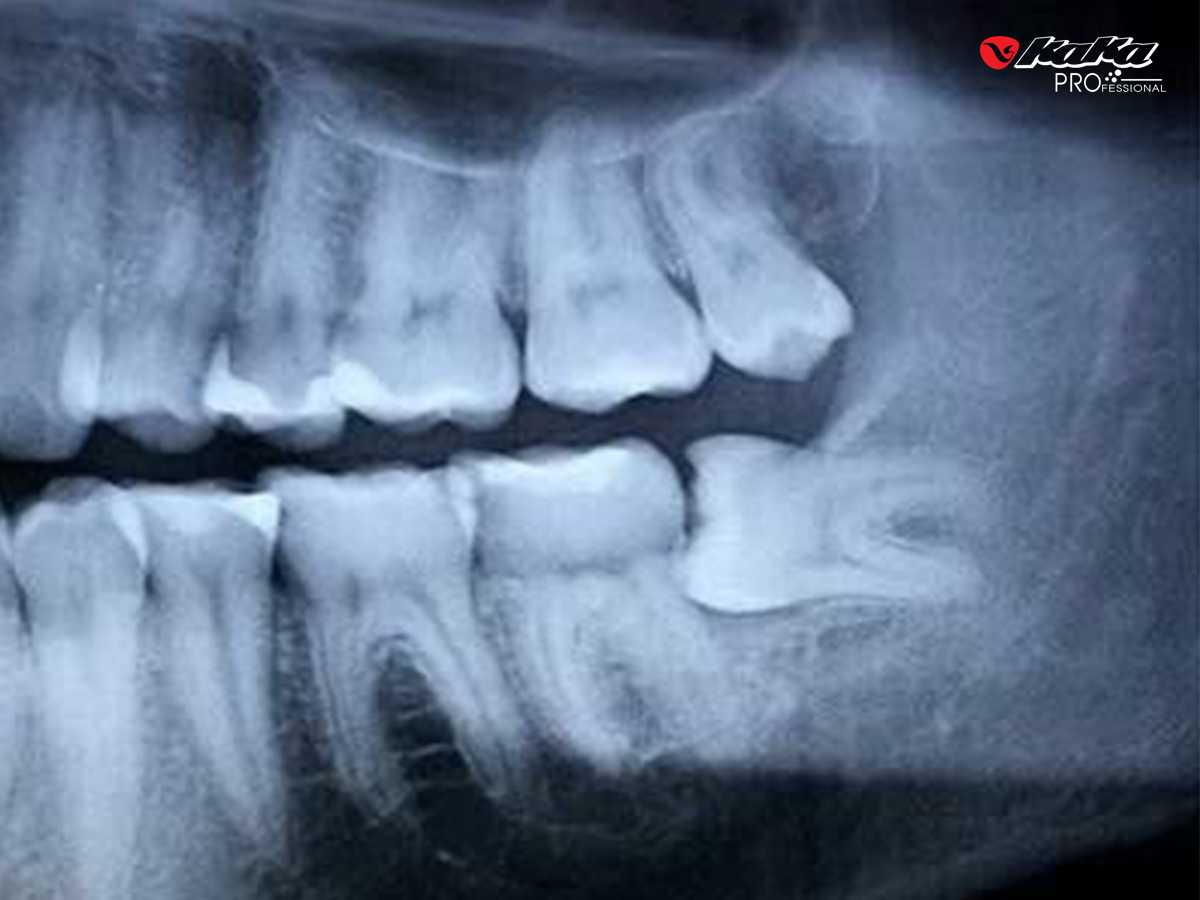

Hình ảnh chụp x-quang của răng khôn mọc lệch

Răng khôn ngầm nghiêng về phía răng số 7 (mesioangular) là loại phổ biến nhất, chiếm khoảng 44% các ca. Răng nghiêng vào trong hoặc ra ngoài má ít gặp hơn. Loại nguy hiểm nhất là răng nằm ngang hoàn toàn (horizontal) là tình trạng răng số 8 mọc song song với xương hàm, chèn ép trực tiếp vào răng số 7, thường ngầm dưới nướu/xương.

Về mức độ chôn vùi: răng mọc ngầm một phần (partially impacted) có một phần mũi răng đã nhô qua nướu nhưng không đủ chỗ để mọc hoàn toàn. Đây thực ra là tình trạng đáng lo hơn răng ngầm hoàn toàn, vì phần nướu hở tạo ra một túi nướu, nơi vi khuẩn và thức ăn dễ tích tụ, gây viêm pericoronitis (viêm nướu trùm răng khôn) tái đi tái lại.